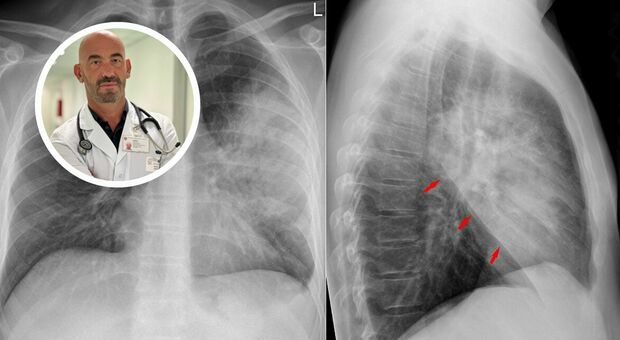

Polmonite, boom di casi. Bassetti: «Ospedali già pieni». Sintomi, cause, cure e cosa non fare

«I nostri ospedali sono già oggi pieni di casi di polmonite», avverte Matteo Bassetti, direttore Malattie infettive dell'ospedale policlinico San Martino di Genova. Ogni... Continua a leggere...